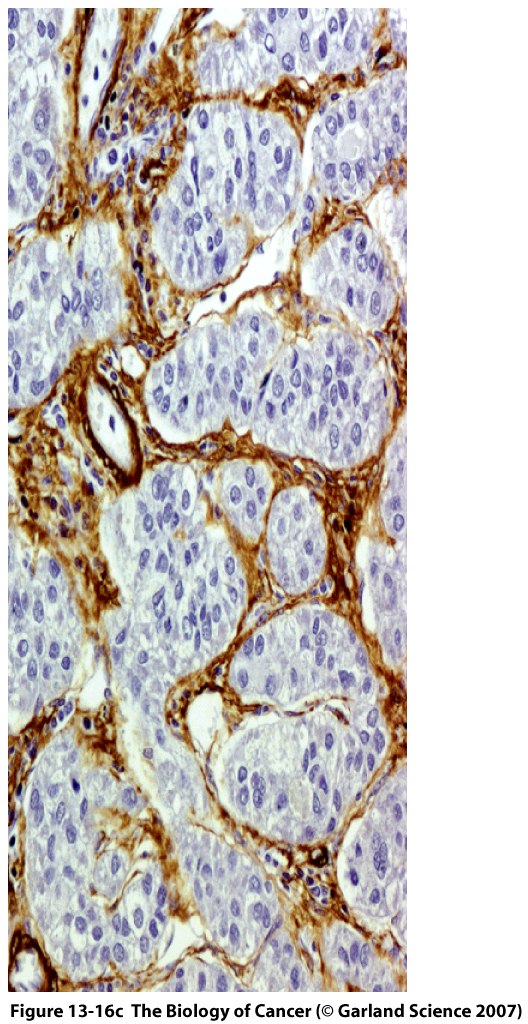

This Concept Map, created with IHMC CmapTools, has information related to: Section 13.3, wounded tissues cause epithelial cells, herceptin reduces relapse of tumors, wound healing attracts mast cells, myofibroblasts are components of tumors, breast cancer surgery stimulates proliferation of micrometastases, fibrocytes can turn to myofibroblasts, angiogenesis aka neoangiogenesis, tissue factor mediates fibrin bundles, tumors resemble wound healing, myofibroblasts assist wound healing, tumor-associated stroma has leaky venules, vasoactive factors initiate formation of the blood clot, eosinophils initiate angiogenesis, desmoplastic stroma instead of normal stroma, epithelial-mesenchymal transition and then MET, serum-activated fibroblasts as determined by functional genomics, fibrocytes can turn to fibroblasts, monocytes initiate angiogenesis, adherens junctions hold together epithelial cells, herceptin blocks HER2/Neu receptor